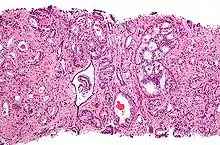

Gleason pattern 4 (left of image) and Gleason pattern 5 (right of image). H&E stain.

• Pattern 4 - The tissue has few recognizable glands. Many cells are invading the surrounding tissue in neoplastic clumps. This corresponds to a poorly differentiated carcinoma.

• Pattern 5 - The tissue does not have any or only a few recognizable glands. There are often just sheets of cells throughout the surrounding tissue. This corresponds to an anaplastic carcinoma.

Gleason pattern 4 glands are no longer single/separated glands like those seen in pattern 1-3. They look fused together, difficult to distinguish, with rare lumen formation vs Gleason 1-3 which usually all have open lumens (spaces) within the glands, or they can be cribriform-(resembling the cribriform plate/similar to a sieve. An item with many perforations). Fused glands are chains, nests, or groups of glands that are no longer entirely separated by stroma-(connective tissue that normally separates individual glands in this case). Fused glands contain occasional stroma giving the appearance of "partial" separation of the glands. Due to this partial separation, fused glands sometimes have a scalloped (think looking at a slice of bread with bite taken out of it) appearance at their edges.[3][6]

Gleason 5

Neoplasms have no glandular differentiation (thus not resembling normal prostate tissue at all). It is composed of sheets (groups of cells almost planar in appearance (like the top of a box), solid cords (group of cells in a rope like fashion running through other tissue/cell patterns seen), or individual cells. You should not see round glands with lumenal spaces that can be seen in the other types that resemble more the normal prostate gland appearance.[3][6]